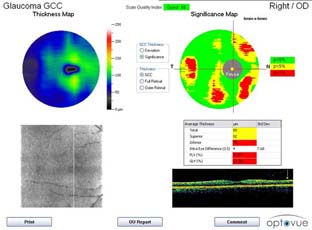

Současné zobrazovací metody glaukomu považujeme za velmi přínosné pro stanovení diagnózy glaukomu a sledování vývoje onemocnění v čase. Těmito metodami sledujeme objektivně projevy glaukomové neuropatie včetně její progrese.